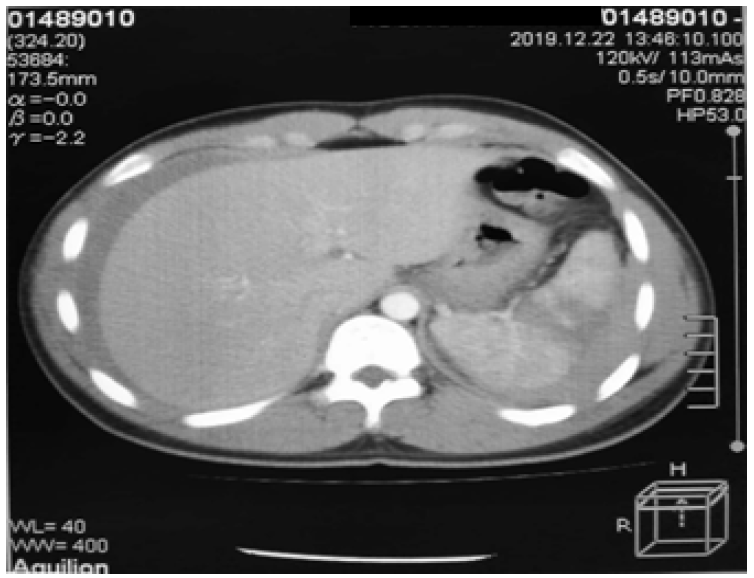

Later, the patient was sent to radiology for abdominal CT examination, and the results showed liver rupture grade IV and splenic rupture grade II (AAST rating scale), with free fluid in the abdominal cavity (Hematoperitoneum) (Figure 6).

Figure 6: Liver Rupture Grade IV and Splenic Rupture Grade II (AAST Rating Scale), Free Fluid in the Abdominal Cavity

In this case, the patient showed FAST (+) results in the Morison pouch and Splenorenal pouch. The FAST ultrasound results were then followed by a contrast CT scan of the abdomen and obtained liver rupture grade IV, splenic rupture grade II, and free intra-abdominal fluid. In this case, the (+) result in Morison pouch was accompanied by liver rupture grade IV, while the (+) result in Splenorenal was accompanied by splenic rupture grade II.